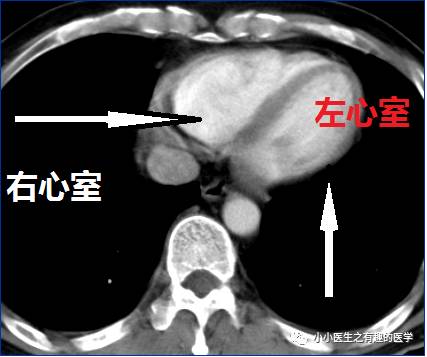

7.要知道左心房、左心室、右心房、右心室,因为这个层面,一般就是中叶、下叶基底段,不再是背段,上叶也几乎不在这里了。

四个心腔,很简单,在下边的是左心房,左心房和左心室相连。右边也如此,心室都在病人左侧。

8.要知道左心室、右心室,这是划分肺段的主要依据之一。